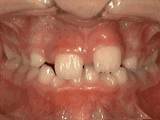

爱美之心,人皆有之~~5月份世界正畸日即将来临,暑假还远吗?分院提前给爱美的你准备好一份大大的福利,还等什么呢?抓紧约起来吧! 发现自己牙齿不整齐影响交际, 怎么还能与小伙伴愉快地玩耍? 无论是即将迈入新的年级还是即将面临找工作, 发现自己是“地包天”“龅牙妹”, 分分钟拉远自己和同龄人的距离! 这些难以启齿的牙齿问题, 想想就让人心碎,怎么办呢? 不要着急,不要慌乱! 这个时候, 你可能需要的就是牙齿矫正了~! 以下图片告诉你, 这些情况都适合去做牙齿矫正哦~! 前牙移位 症状表现:牙齿缺失、牙周疾病等导致相邻牙齿无秩序前突 牙列拥挤 症状表现:牙齿过多,牙槽骨过窄,使牙齿没有足够空间生长造成牙齿排列不齐 开颌 症状表现:通俗来讲就是咬牙时无法紧闭,上下牙齿中间有缝 上牙深覆合 症状表现:上牙边沿覆盖下牙超过1/3,俗话说的天包地 后天牙列稀疏 症状表现:疾病外因等造成的牙列稀疏,牙槽骨过长或牙齿缺失,导致排列太宽松,零零散散 前牙反合 症状表现:下牙边沿覆盖上牙超过1/3,俗话说的地包天 天生牙列稀疏 症状表现:天生的牙列稀疏,牙槽骨过长,牙缝过宽、牙齿较少(一般不缺牙),导致排列宽松,零零散散 以上几种情况有你么? 要知道一口整齐的牙齿 绝对能够把整体的颜值提升N个档次! 如果你不幸中招, 就好好利用这个正畸月, 来分院加入到正畸大军里吧! 牙齿正畸也叫做牙齿矫正,原理简单来讲呢,就是对牙齿施加一个合适的外力(一般通过矫正器来施加),这个力会通过牙齿传递到牙齿周围的牙槽骨上,使得代谢很活跃的牙槽骨发生改建,从而带动牙齿一起缓慢移动。其治疗效果有着肉眼可见的强大变化! 借此正畸月,分院为大家准备了正畸月大放价,暑假提前约的活动!!!如果还想了解更多关于牙齿矫正的信息,欢迎大家来到分院进行咨询哦~我们的专业团队会帮您定制最适合自己的矫正方案,活动月矫正方案免费送哦!定能助您改“斜”归“正”!露出灿烂自信的笑容!